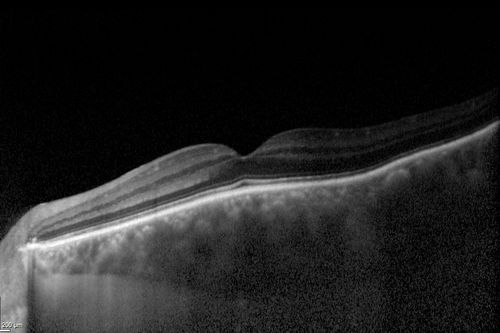

Choroidal Hemangioma - Diffuse - Enhanced Depth Imaging Spectral Domain OCT Line Scan - Abnormal Eye

Choroidal Thickness is 697 Microns from Diffuse Choroidal Hemangioma